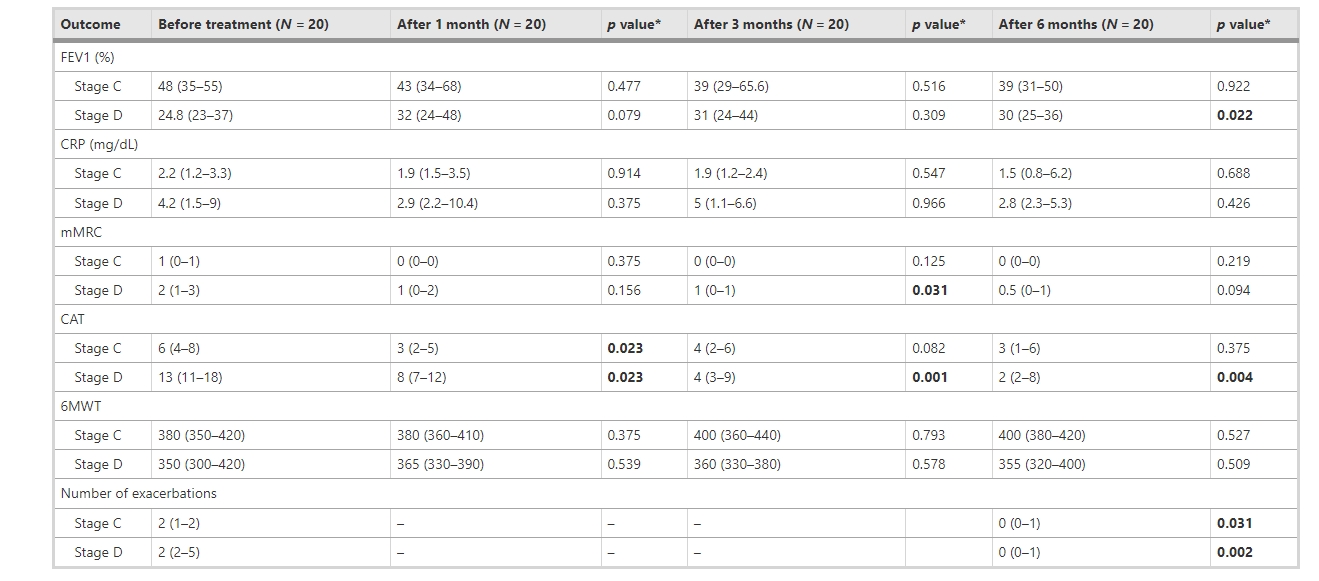

共有20名患者入組。根據(jù)??全球阻塞性肺病倡議 (GOLD) 分類,9名患者為C期,11名患者為D期。

有效性評(píng)估

1.根據(jù)GOLD分期進(jìn)行治療前和隨訪期間的臨床結(jié)果評(píng)估

- 治療前(34%) 和治療后1(35%)、3 (33.0%) 和6(33.5%) 個(gè)月的FEV1均略有改變 (p>0.05)。

- 平均CRP水平從治療前的3.3mg/dL分別下降到治療后1、3和6個(gè)月的2.2、2.4和2.3 (mg/dL)。

- 6MWT從治療前的360.0分別增加到治療后1、3 和 6 個(gè)月的380、360.0和380.0 (p>0.05)。

- 與治療前相比,治療后1、3 和6個(gè)月的mMRC、CAT評(píng)分和發(fā)作次數(shù)均顯著下降,且這種下降趨勢(shì)在治療后1~6個(gè)月內(nèi)持續(xù)。

- 治療后1、3和6個(gè)月,mMRC值從治療前的1.0顯著下降為0.0(p<0.05)。

- 同樣,CAT評(píng)分也從治療前的10.05顯著下降為治療后1個(gè)月的6.5、治療后3個(gè)月的4.0和治療后6個(gè)月的2.0(p<0.05)。COPD發(fā)作次數(shù)從治療前的2次顯著減少為治療后6個(gè)月的0(p<0.05)。

2.C期和D期患者的療效評(píng)估

- 圖7和表4顯示了結(jié)果,表明UC-MSC移植對(duì)D期COPD患者的治療效果優(yōu)于C期COPD患者。

- D期COPD患者治療3個(gè)月后mMRC、CAT值較治療前明顯改善,治療6個(gè)月后FEV1、CAT評(píng)分、發(fā)作次數(shù)較治療前明顯改善(P<0.05)。

- 6個(gè)月后兩組CRP值較治療前均下降約40%。

安全性評(píng)估:UC-MSC輸注耐受性良好,所有患者在研究或藥物輸注過(guò)程中均未觀察到嚴(yán)重或臨床顯著的不良事件。

綜上所述,未發(fā)生與UC-MSC給藥相關(guān)的輸注毒性、死亡或嚴(yán)重不良事件。接受UC-MSC移植的患者的改良醫(yī)學(xué)研究委員會(huì)評(píng)分、COPD評(píng)估測(cè)試和加重次數(shù)均顯著降低。

結(jié)論:系統(tǒng)性UC-MSC治療對(duì)中度至重度COPD患者似乎是安全的,可以顯著改善他們的生活質(zhì)量,并為后續(xù)的細(xì)胞治療研究提供基礎(chǔ)。